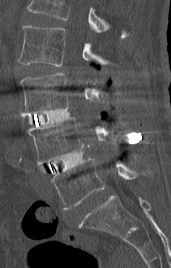

第1腰椎椎体骨折を認めます。MRI検査では圧潰が高度で骨片が後方の神経を圧迫しているのが分かります。強い腰痛、下肢しびれ、不全麻痺により歩けない状態でした。

後方から圧潰した椎体を取り除き神経を除圧して、金属の支柱による椎体置換術を施しました。上下の椎体は骨粗鬆症により脆弱であったため、セメント補強スクリューを使用して引き抜き強度を上げました。固定性が良好なため、術後すぐに離床、歩行訓練を行うことが出来ています。